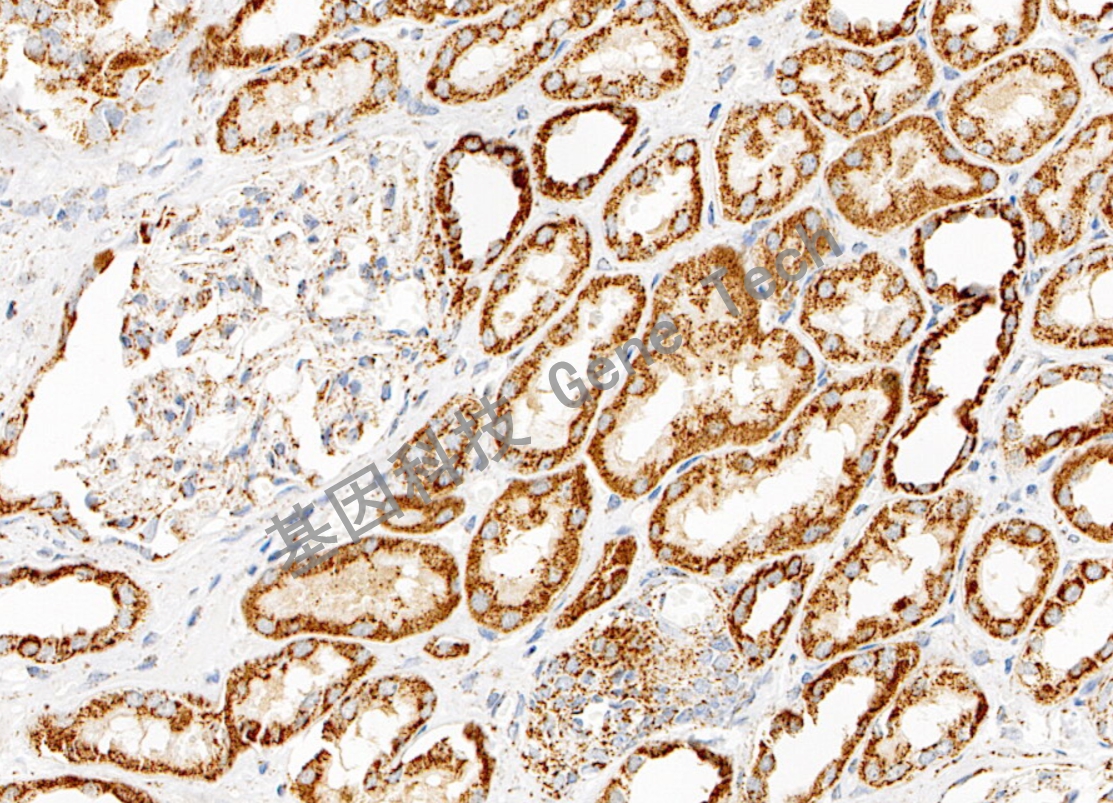

| 腎癌石蠟切片,用 FH(GT2444)染色,細(xì)胞漿陽性,DAB 顯色。 | ||

| 預(yù)處理:高pH熱修復(fù) | 陽性部位:細(xì)胞漿 | 陽性對照:腎癌 |